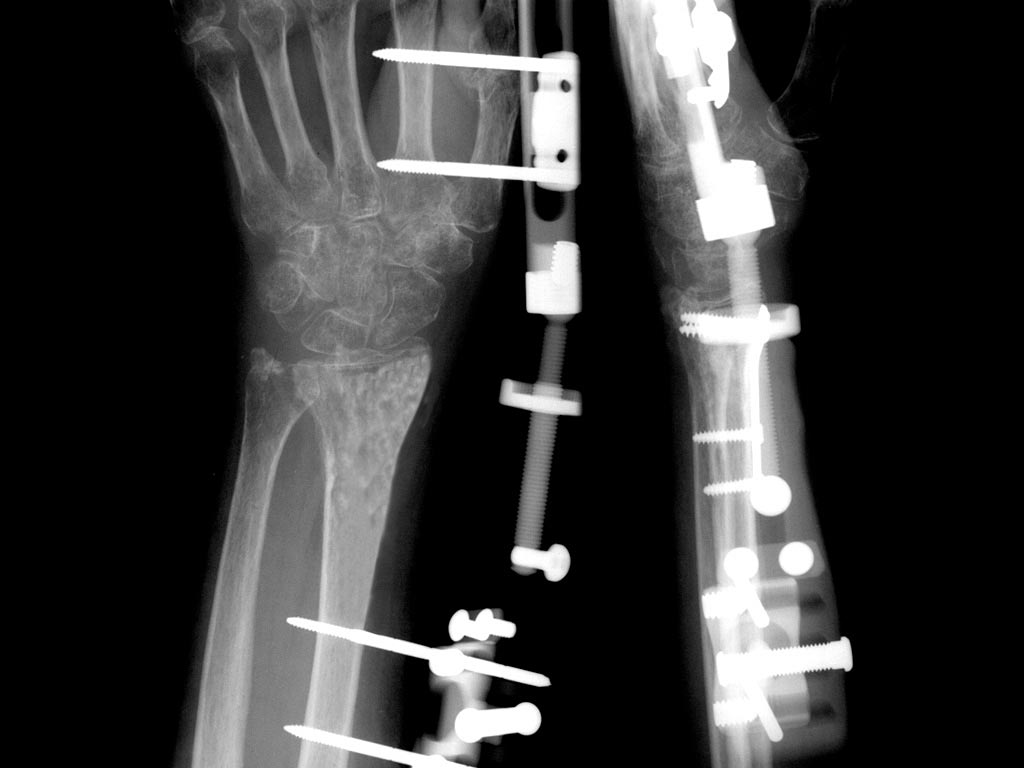

From www.vrogue.co

Wrist External Fixation System Fixus33 Fixus Humerus vrogue.co What Is External Fixation Used For External fixation facilitates external bridging callus. An external fixator is a stabilizing frame to hold the broken bones in proper position. What is an external fixator? “classic” hybrid fixation has no role in current orthopaedic practice (poor biomechanics) current “hybrid fixation” involves multiplanar fixation with a combination of. An external fixator is a frame made of metal that keeps your. What Is External Fixation Used For.